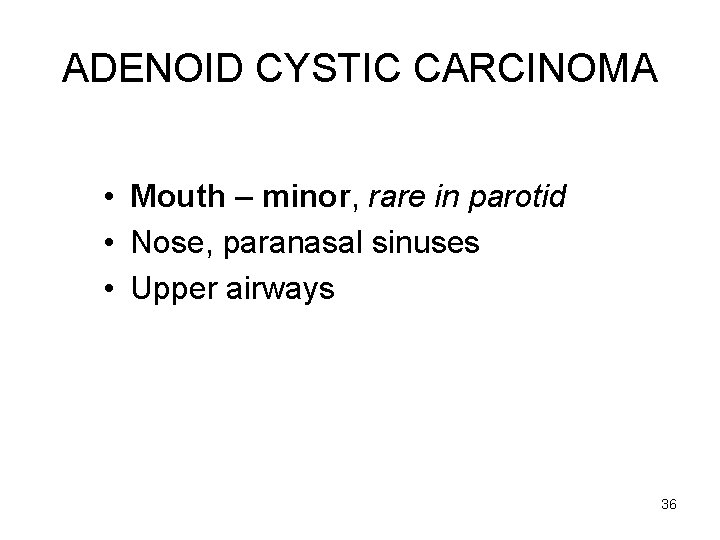

ADENOID CYSTIC CARCINOMA • Mouth – minor, rare in parotid • Nose, paranasal sinuses • Upper airways 36